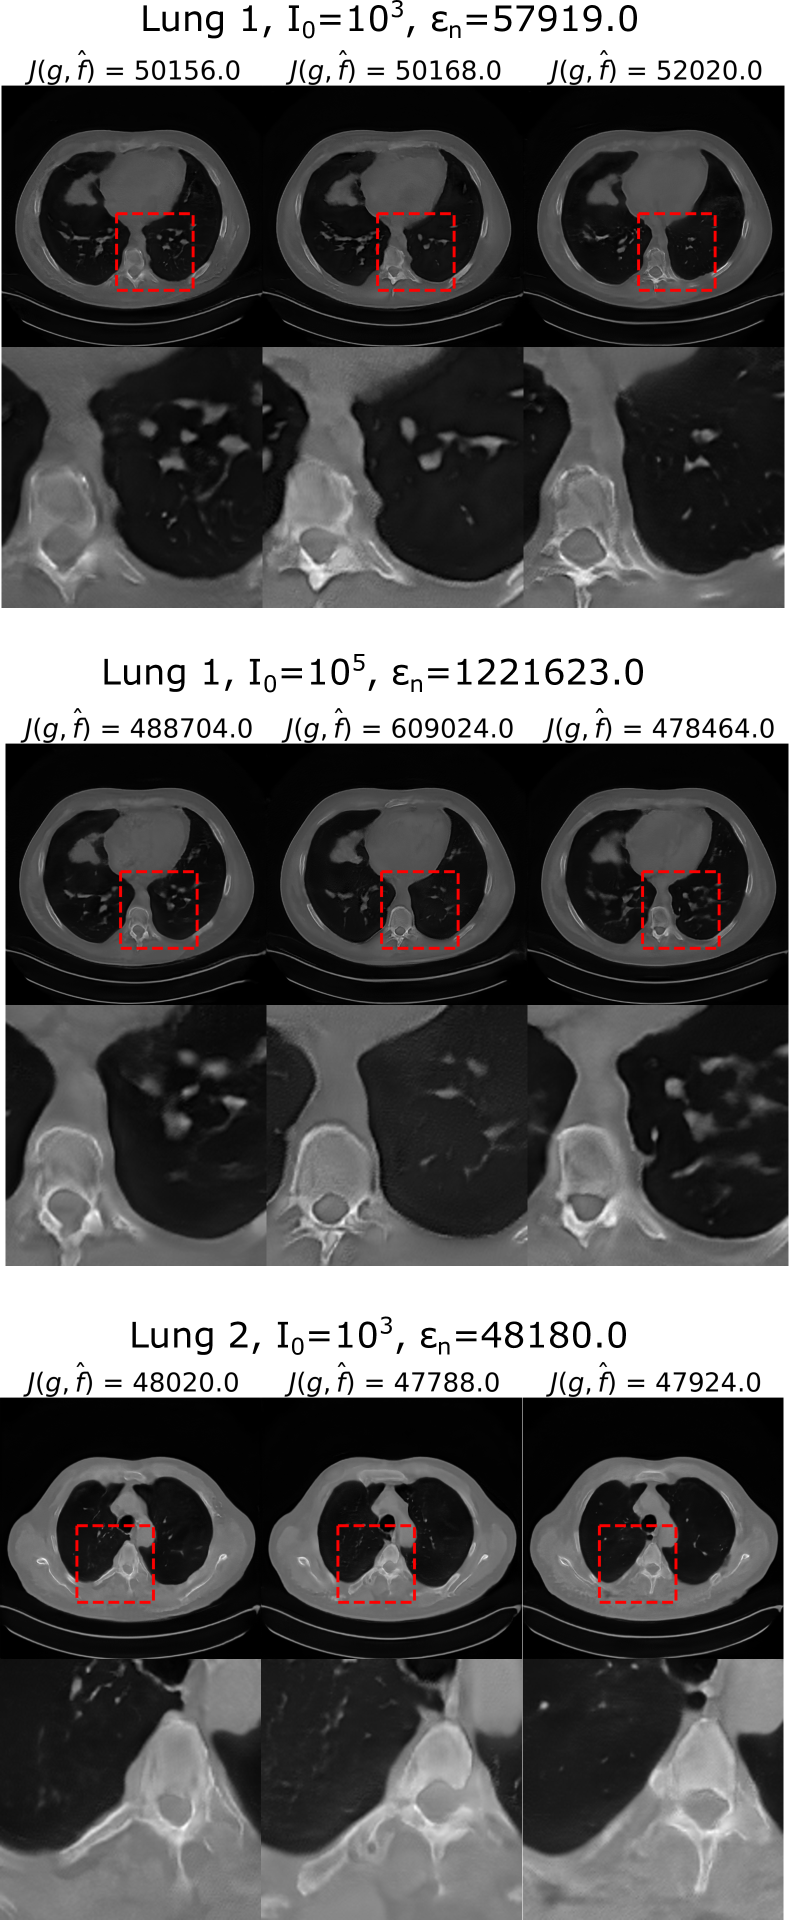

Samples of data-consistent alternate solutions obtained with the PULSE++ method using the same CT-StyleGAN model are shown in Fig. 9, corresponding to limited-angle projection data from Lung 1 (I0=103subscript𝐼0superscript103I_{0}=10^{3}, I0=105subscript𝐼0superscript105I_{0}=10^{5}) and Lung 2 (I0=103subscript𝐼0superscript103I_{0}=10^{3}). Additional alternate solutions are provided in the supplementary material described in the Appendix. The alternate solutions in each case displayed considerable variability in fine-scale structures. This illustrates the ability of the proposed PULSE++ method to produce diverse data-consistent solutions from the same measurement data for high-dimensional objects, which may be computationally infeasible with currently available posterior sampling methods.

Refer to caption

Figure 9: Alternate data-consistent solutions obtained using the PULSE++ method using the CT-StyleGAN model under different settings, for projection data from Lung 1 (I0=103subscript𝐼0superscript103I_{0}=10^{3}, I0=105subscript𝐼0superscript105I_{0}=10^{5}) and Lung 2 (I0=103subscript𝐼0superscript103I_{0}=10^{3}). Zoomed-in images of the same region in the alternate solutions inside the red bounding box demonstrate diversity in a number of fine-scale structures. The grayscale range of the alternate solutions is [0,1].